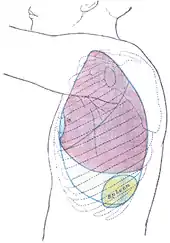

The spleen is underneath the left part of the diaphragm, and has a smooth, convex surface that faces the diaphragm. It is underneath the ninth, tenth, and eleventh ribs. The other side of the spleen is divided by a ridge into two regions: an anterior gastric portion, and a posterior renal portion. The gastric surface is directed forward, upward, and toward the middle, is broad and concave, and is in contact with the posterior wall of the stomach. Below this it is in contact with the tail of the pancreas. The renal surface is directed medialward and downward. It is somewhat flattened, considerably narrower than the gastric surface, and is in relation with the upper part of the anterior surface of the left kidney and occasionally with the left adrenal gland.

An easy way to remember the anatomy of the spleen is the 1×3×5×7×9×10×11 rule. The spleen is 1 by 3 by 5 inches (3 by 8 by 13 cm), weighs approximately 7 oz (200 g), and lies between the 9th and 11th ribs on the left-hand side and along the axis of the 10th rib. The weight varies between 1 oz (28 g) and 8 oz (230 g) (standard reference range),[12] correlating mainly to height, body weight and degree of acute congestion but not to sex or age.[13]

Back of lumbar region, showing surface markings for kidneys, ureters, and spleen Side of thorax, showing surface markings for bones, lungs (purple), pleura (blue), and spleen (green)

Side of thorax, showing surface markings for bones, lungs (purple), pleura (blue), and spleen (green)